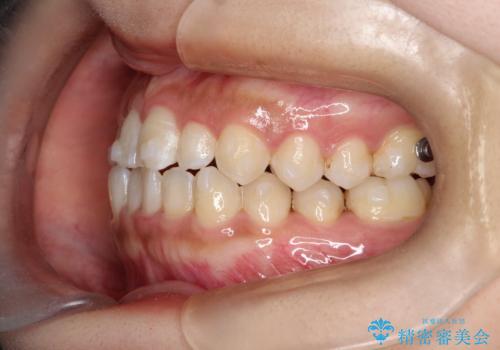

- 前歯の凸凹を主訴に来院された患者様です。

カウンセリング時に、側切歯が矮小歯であることを指摘したところ、適切な幅径での修復を希望されました。

インビザラインを用い、計画通りに歯並びを改善することができました。

矮小歯の幅径を大きくすることで、より理想的な噛み合わせを作ることができます。